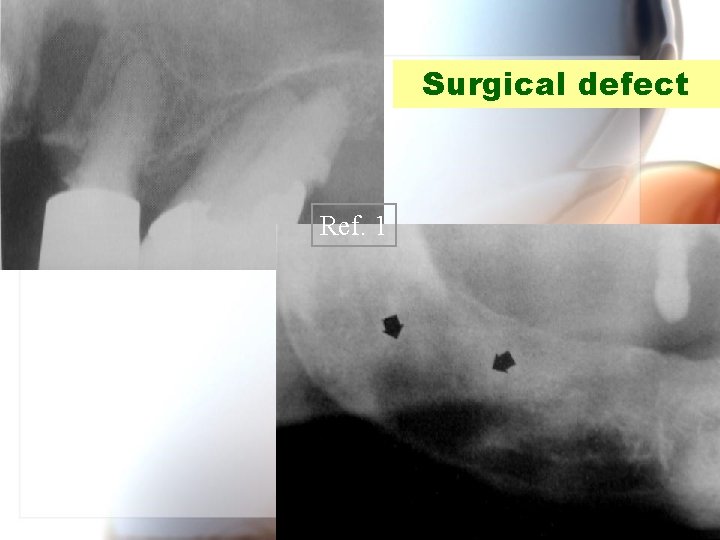

Surgical defect Ref. 1 Wen. Chen Wang